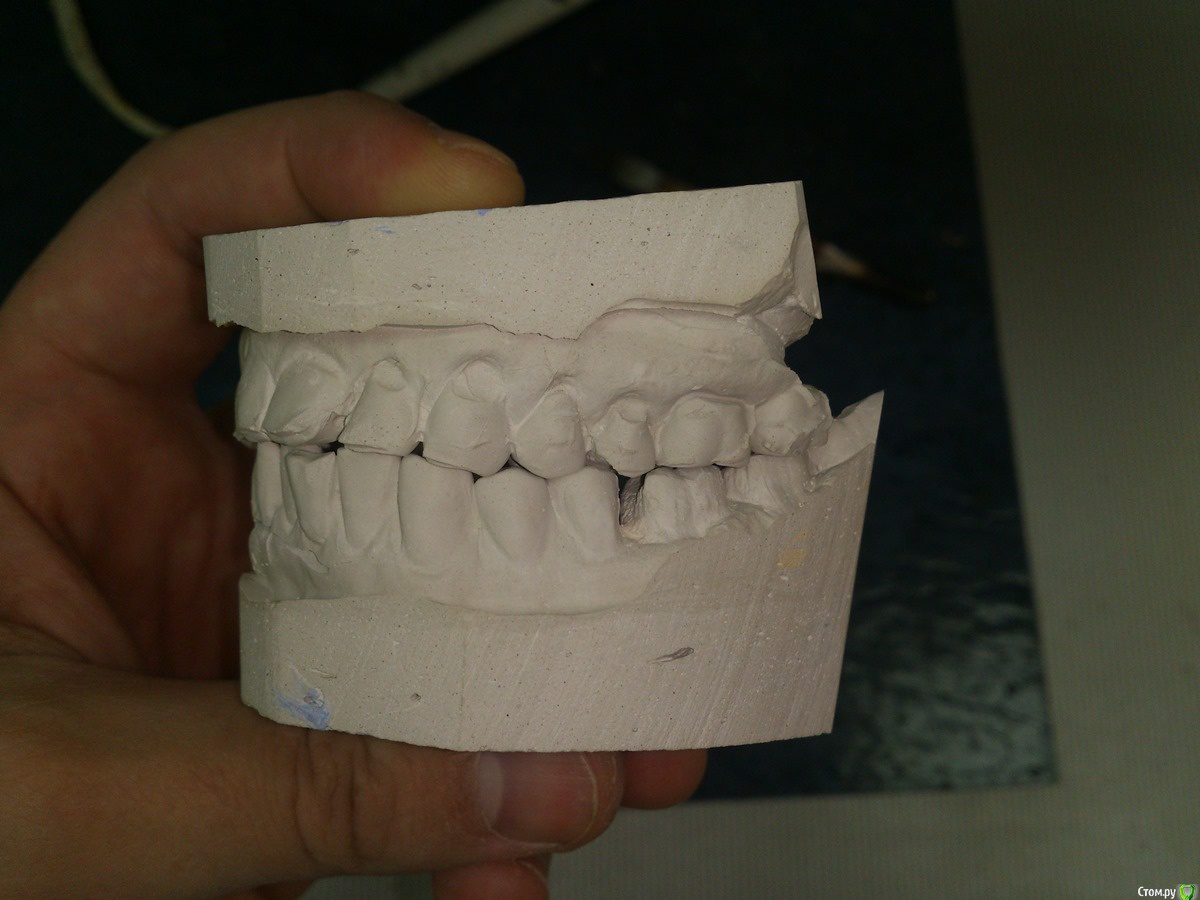

SanderS Опубликовано 6 февраля, 2016 Поделиться Опубликовано 6 февраля, 2016 Пациенту не нравится фронт и пришеечные дефекты, перелечены несколько зубов. Из анамнеза - привычка "стискивать зубы", или как говорит - "попадаю на какой то зуб и начинаю двигать челюсть влево вправо не задумываясь", появилось лет 10 назад, сейчас 35.Возможно обойтись без тотала с каппой, или не браться вообще? Ссылка на комментарий

Sampson Опубликовано 7 февраля, 2016 Поделиться Опубликовано 7 февраля, 2016 Если без тотала.1)Снимок. Уз чистка2)Стераемость 13.23/33.43.Востанавливаем клыковую направляющую.3)Эндолечение и попутное поднятие прикуса на накусочных площадках. 4)Времянки Ссылка на комментарий

Ronin Опубликовано 7 февраля, 2016 Поделиться Опубликовано 7 февраля, 2016 Решение оптимальное, как сказал коллега выше, восстановить фронт и клыковое ведение, но как ограничиться этим, ведь бока тоже нужно делать.. там же эндо, как я понял и так делается, одного моляра нет?! реставрации композиционные что ли? Надо учитывать "стискивание" , разломает потом эти зубы и все, плюс расхождение зубов тоже есть, перегрузка, не забудем и про пародонтальный комплекс, высоту поднять, если нужно, предварительно определив, хотя высота, как мне кажется в порядке, но могу ошибаться, на завершающем этапе обязательно каппу, ношение максимальное время! Здесь важно хуже не сделать, если нет уверенности в стабильном результате, ибо не навреди... Если уверенны, то только в путь))) Ссылка на комментарий

SanderS Опубликовано 8 февраля, 2016 Автор Поделиться Опубликовано 8 февраля, 2016 те что после перелечивания естественно будут покрываться коронками, нижний моляр имплантат, если пришеечные дефекты реставрировать композитом при условии восстановления клыковой направляющей + каппа, не повыпадают ли они? Высота у него вроде не снижена, за счет компенсации. Ссылка на комментарий